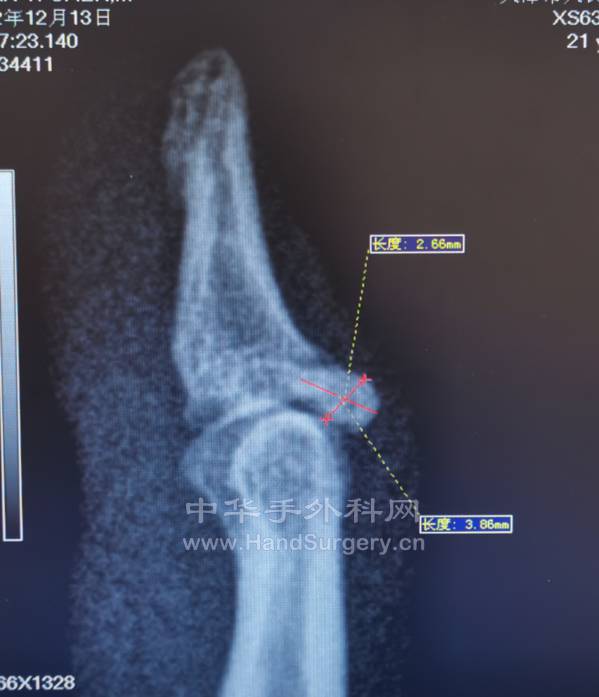

陈旧性骨性锤状指

如何治疗是具有挑战性的!

微信截图_20221215225248.png